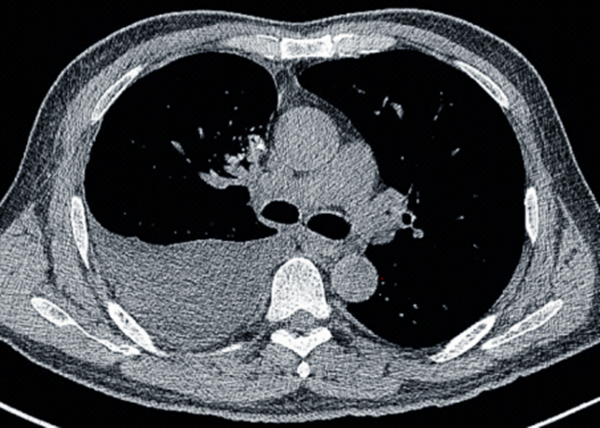

胸部CT平扫提示右侧胸腔大量积液,右肺下叶膨胀不全